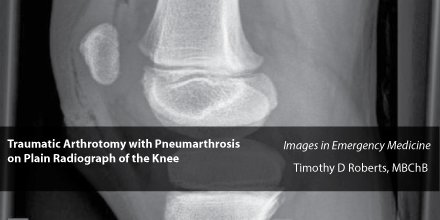

C 2003 by saunders an imprint of elsevier inc. Gas in the joint or pneumarthrosis in the context of trauma is not uncommon around superficial joints such as the knee and indicates that there is a penetrating wound with intra articular extension. Noomah tosis air or gas in an abnormal location in the body.

Westjem On Twitter Foamed Traumatic Arthrotomy With

Pdf Traumatic Arthrotomy With Pneumarthrosis On Plain Radiograph